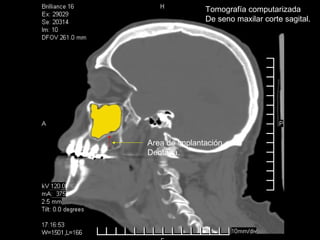

Tomografía computarizada

De seno maxilar corte sagital.

Area de implantación

Dentaria.

Material osteoconductor

para elevar el piso antral

Nuevo piso del seno y su

margen de seguridad para

contener el implante

Tomografía computarizada De senomaxilar corte sagital. Area de implantación Dentaria.

Nuevo piso delseno y su margen de seguridad para contener el implante dentario